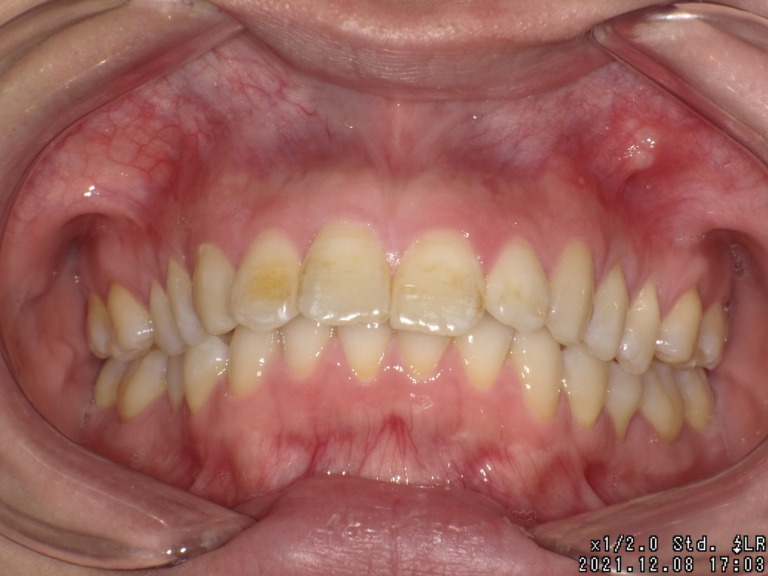

症状 右上八重歯 上顎正中の著しいずれ 通院時の年齢 18才6ヶ月〜21才7ヶ月 通院回数 42回 通院目的 永...

2026.01.27 欠損症例・埋伏歯症例・その他歯の位置異常症例紹介